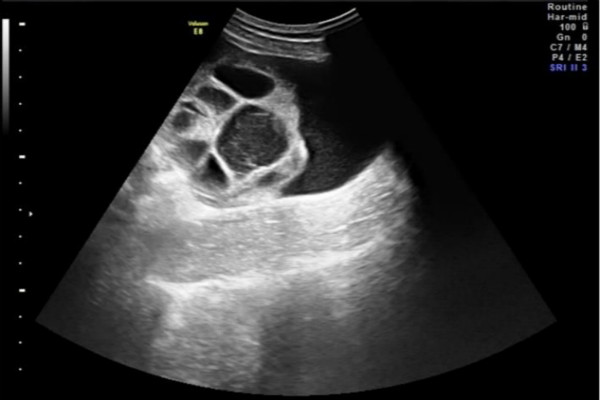

试管婴儿治疗中的卵巢过度刺激综合征(简称OHSS)是由促排卵药物引起的,与患者敏感度、内分泌状态、药物种类及数量、妊娠与否相关。特征为双侧卵巢囊性增大、毛细血管通...

控制性超促排卵方案在取得良好的助孕结局的同时,也存在一些不良反应,如临床比较常见的卵巢过度刺激综合征(ovarian hyper stimulation synd...